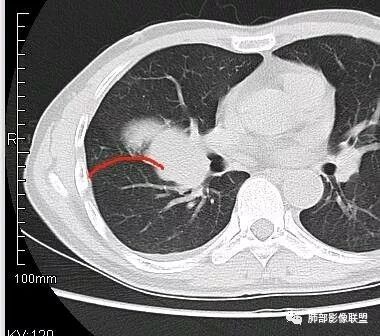

南边:从叶裂的变形,下朝上,越来越朝前扭曲,提示叶裂局部有朝前上推移的趋势

南边:下叶的支气管受压后移、变形

南边:病灶边界清,提示侵袭性弱,膨胀生长为主;这时候我们提示病灶不应该是支气管关系密切,提示间叶来源或胸膜来源

深分叶,警惕恶性